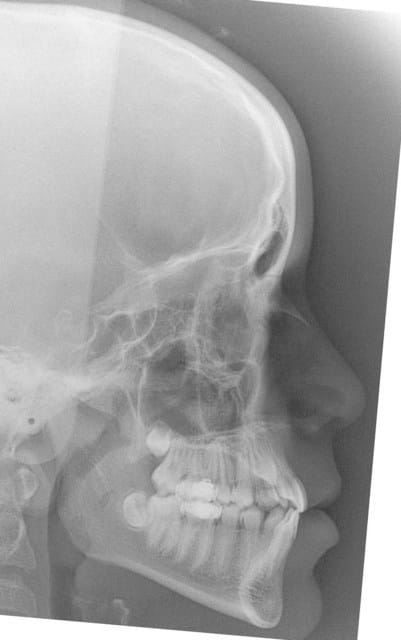

22/05/2008 à 00h10

début 2008,quadhélix en 0.28,pour vestibuler la 2,ce qui est fait

Tele2002 qhiepn - Eugenol

Tele2007 b6yul0 - Eugenol

et les profils

Profil2002 rznvai - Eugenol

Profil2007 dxpeqm - Eugenol